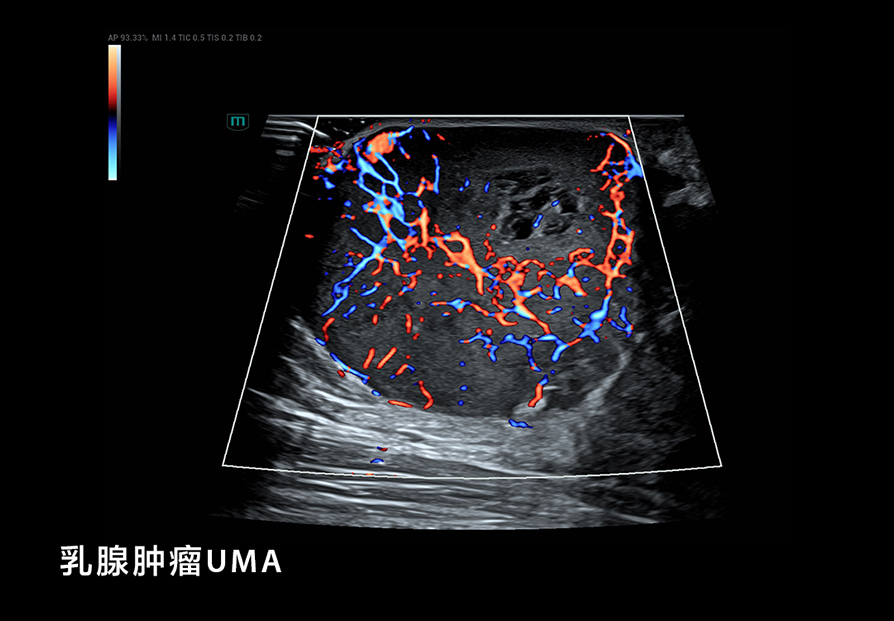

我们在 B-Mode 成像方面考虑了更细(超高频率)、更深(超低频率),更好的对比分辨率,如个异化的 HD Scope,以提高早期鉴别诊断的能力;在超微血流方面, UMA突破传统彩色多普勒的限制,使细微血流的显示达到新的高度;还有创新的血流流变学(VFM)等分析技术,以及流变学与生物力学结合的技术等;在弹性成像方面,我们也有很多可圈可点的地方。我们可以形成多模态,多模式的成像与显示,为临床和科研提供新的工具;在造影成像(CEUS)方面,我们还有极具特色的高帧率造影技术和 CEUS QI 分析系统,还有光声成像等这些新的方向。